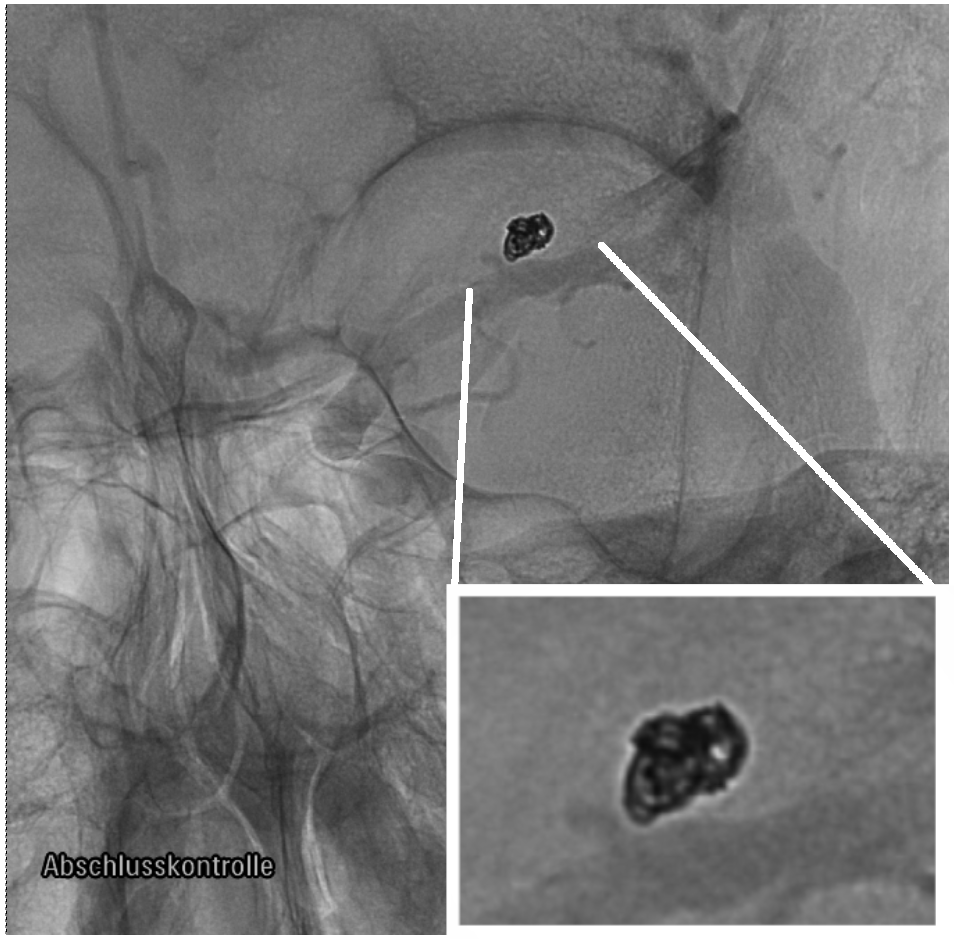

The coiling procedure is conducted under continuous imaging supervision in digital subtraction angiography, a fluoroscopy technique, where an interventionist inserts a catheter through a femoral or radial access to reach for the brain along the upstream of blood, carefully moving to the part where the aneurysm is located. Then, via a micro-catheter, the wire is protruded into the aneurysm dome. Coils do exist in various shapes and sizes as well as with various material properties [23, 27, 51]. A patient-specific choice, e.g., with respect to the length or the imprinted natural shape of the inserted coil(s), is made based on preceding aneurysm measurements as well as the surgeons experience with respect to optimal placement [32]. Possible choices are, e.g., a stiffer framing coil followed by one or several softer filling and finishing coils depending on the shape of the aneurysm, see Fig. 1.

An angiography in combination with the injection of a tracer fluid allows to evaluate the actual occlusion quality and serves as a decision-making tool whether more coiling wires have to be inserted. Typically, a packing density , defined as the volume of the inserted coil relative to the volume of the aneurysm sack , of 20-25 % is desired [47], with the coil sitting tightly within the aneurysm, not protruding into the parent vessel. As soon as the aneurysm is sufficiently packed, the catheter is retracted from the aneurysm and clot-formation is about to begin. The presence of a sufficient amount of coil within the aneurysm reduces the perfusion of the aneurysm sack. This effect is even further enhanced by a growing thrombus, eventually

We would like to express our gratitude to Prof. Jan Kirschke and Dr. Julian Schwarting of the Hospital Rechts der Isar in Munich for generously providing us two images of the coiling procedure for an aneurysm shown in Fig. 1. Their expertise as neuroradiologists and their invaluable contributions have greatly enriched this work.